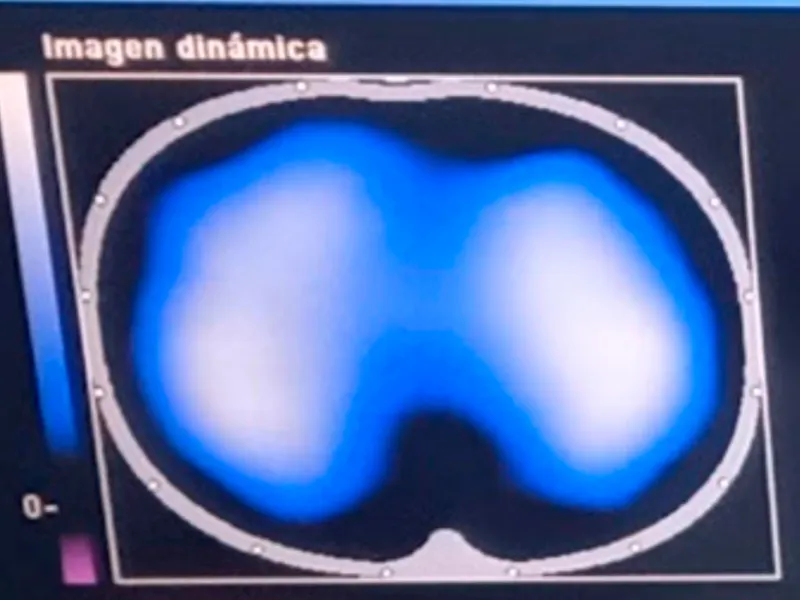

Imágenes de tomografía que se toman para analizar el desempeño de la fisioterapia con el incentivo de re-expansión pulmonar. El área de color azul-blanco representa el volumen del pulmón en un corte transversal, visto desde arriba, cuanto mayor aire llega a los pulmones se expande el pulmón y llega aire a zonas al pulmón que originalmente no se utilizaban.

Imágenes de tomografía que se toman para analizar el desempeño de la fisioterapia con el incentivo de re-expansión pulmonar. El área de color azul-blanco representa el volumen del pulmón en un corte transversal, visto desde arriba, cuanto mayor aire llega a los pulmones se expande el pulmón y llega aire a zonas al pulmón que originalmente no se utilizaban.

Imágenes de tomografía que se toman para analizar el desempeño de la fisioterapia con el incentivo de re-expansión pulmonar. El área de color azul-blanco representa el volumen del pulmón en un corte transversal, visto desde arriba, cuanto mayor aire llega a los pulmones se expande el pulmón y llega aire a zonas al pulmón que originalmente no se utilizaban.